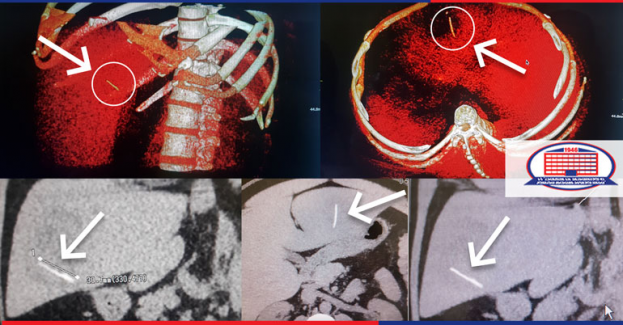

დეპარტამენტი სრულადაა აღჭურვილი სარეანიმაციო მოწყობილობებით. აქ არის გადაუდებელი დახმარებისა და ინტენსიური თერაპიის წარმოებისათვის აუცილებელი ყველა ტიპის სამედიცინო აპარატურა, 24/7-ის რეჟიმში პაციენტების განკარგულებაშია ულტრათანამედროვე რენტგენოგრაფი, ექოსკოპები APLIO 400 და APLIO 500, TOSHIBA-ს ფირმის კომპიუტერული და მაგნიტურ–რეზონანსული ტომოგრაფი, ანგიოგრაფი Shimadzu–ს წარმოების Trinias B12, რომელიც პირველად გაიყიდა იაპონიის საზღვრებს გარეთ და ექსკლუზიურია ჩვენს რეგიონში (ამიერკავკასიაში), რაც საშუალებას გვაძლევს წარმატებით ვაწარმოოთ ნებისმიერი ტიპის ენდოვასკულური მანიპულაციები და ოპერაციები კარდიო, ნეირო და ანგიოვასკულური ინტერვენციების სახით.

24 საათის განმავლობაში გადაუდებელი ჩარევების რეჟიმშია შესაძლებელი კორონარების, თავის ტვინის და სხვა არტერიების გამოკვლევა და სტენტირება. ამ აპარატურას ემსახურებიან ადგილზე მყოფი გამოცდილი და პროფესიონალი სპეციალისტები. 24 საათის განმავლობაში გამართულად მუშაობს ულტრათანამედროვე ლაბორატორია, რომელშიც შესაძლებელია ყველა ლაბორატორიული კვლევის ჩატარება შეუფერხებლად.